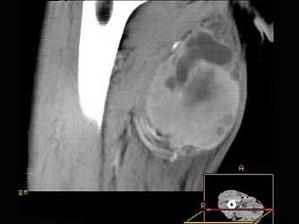

问题 男,30岁,主诉右大腿肿块年余,逐渐增大,局部胀痛及压痛,请根据图像表现,选出最佳选项 ( )

选项 A、横纹肌肉瘤 B、神经纤维瘤 C、血管瘤 D、脂肪瘤 E、脓肿

答案 A